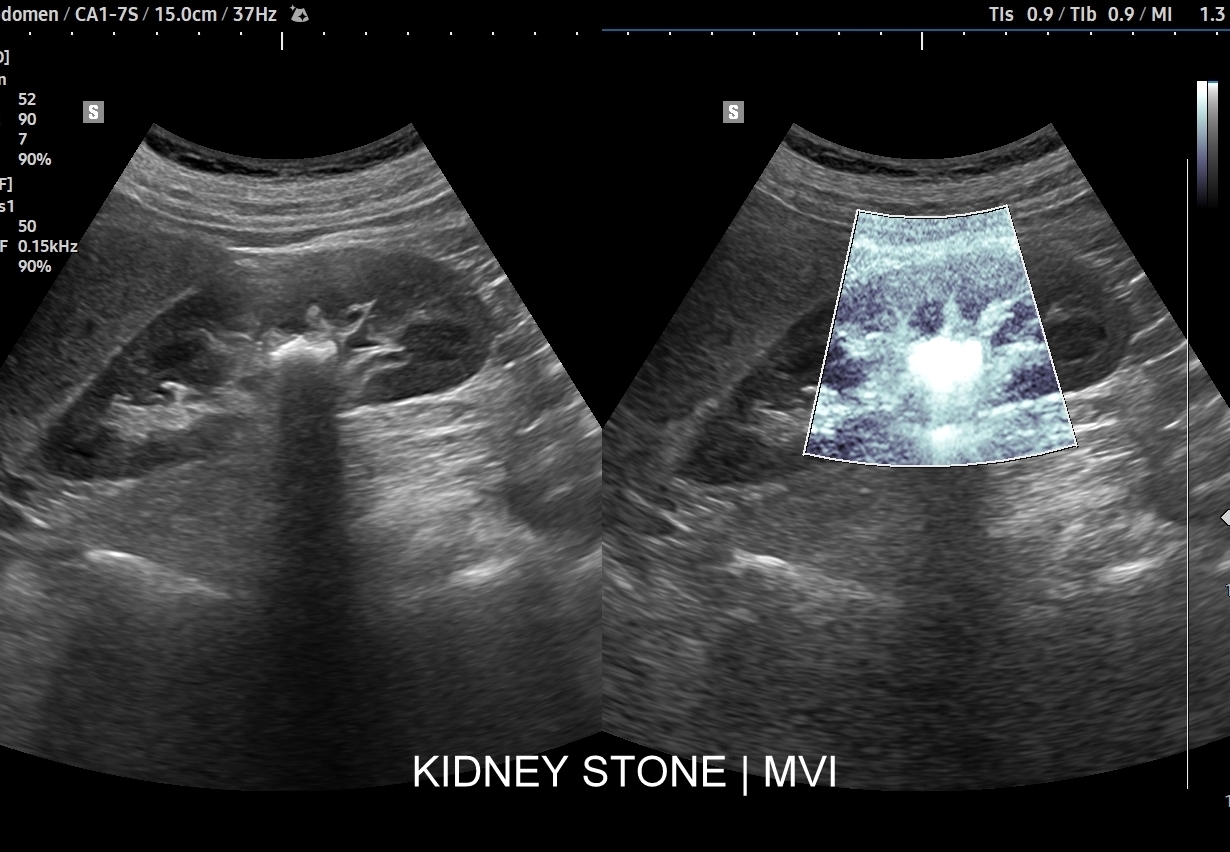

Badania obrazowe służące wykrywaniu kamicy moczowej to badanie RTG, CT, lecz przede wszystkim badanie USG. W badaniu USG nerek w prezentacji B kamica nerkowa widoczna jest w sytuacji, gdy złogi są odpowiednio uwapnione, odpowiednio duże oraz nie zlewają się z zatoką tłuszczową miedniczki nerki. Zasadniczo złogi w trybie B będą widoczne wyraźniej, gdy położone są w miąższu nerki; z kolei w miedniczce nerkowej, gdy są na tyle duże, że dają artefakt cienia. Czasem w celu uwidocznienia złogu przydatne jest wyłączenie wspomagania typu x-beam.

Ważnym trybem pomocniczym jest color-Doppler, w którym to trybie uzyskuje się tzw. artefakt migotania, często nawet na bardzo drobnych złogach niewidocznych w trybie B. Uzyskanie efektu migotania jest niestety zależne o jakości aparatury USG, a także od ustawień Dopplera i software’u.